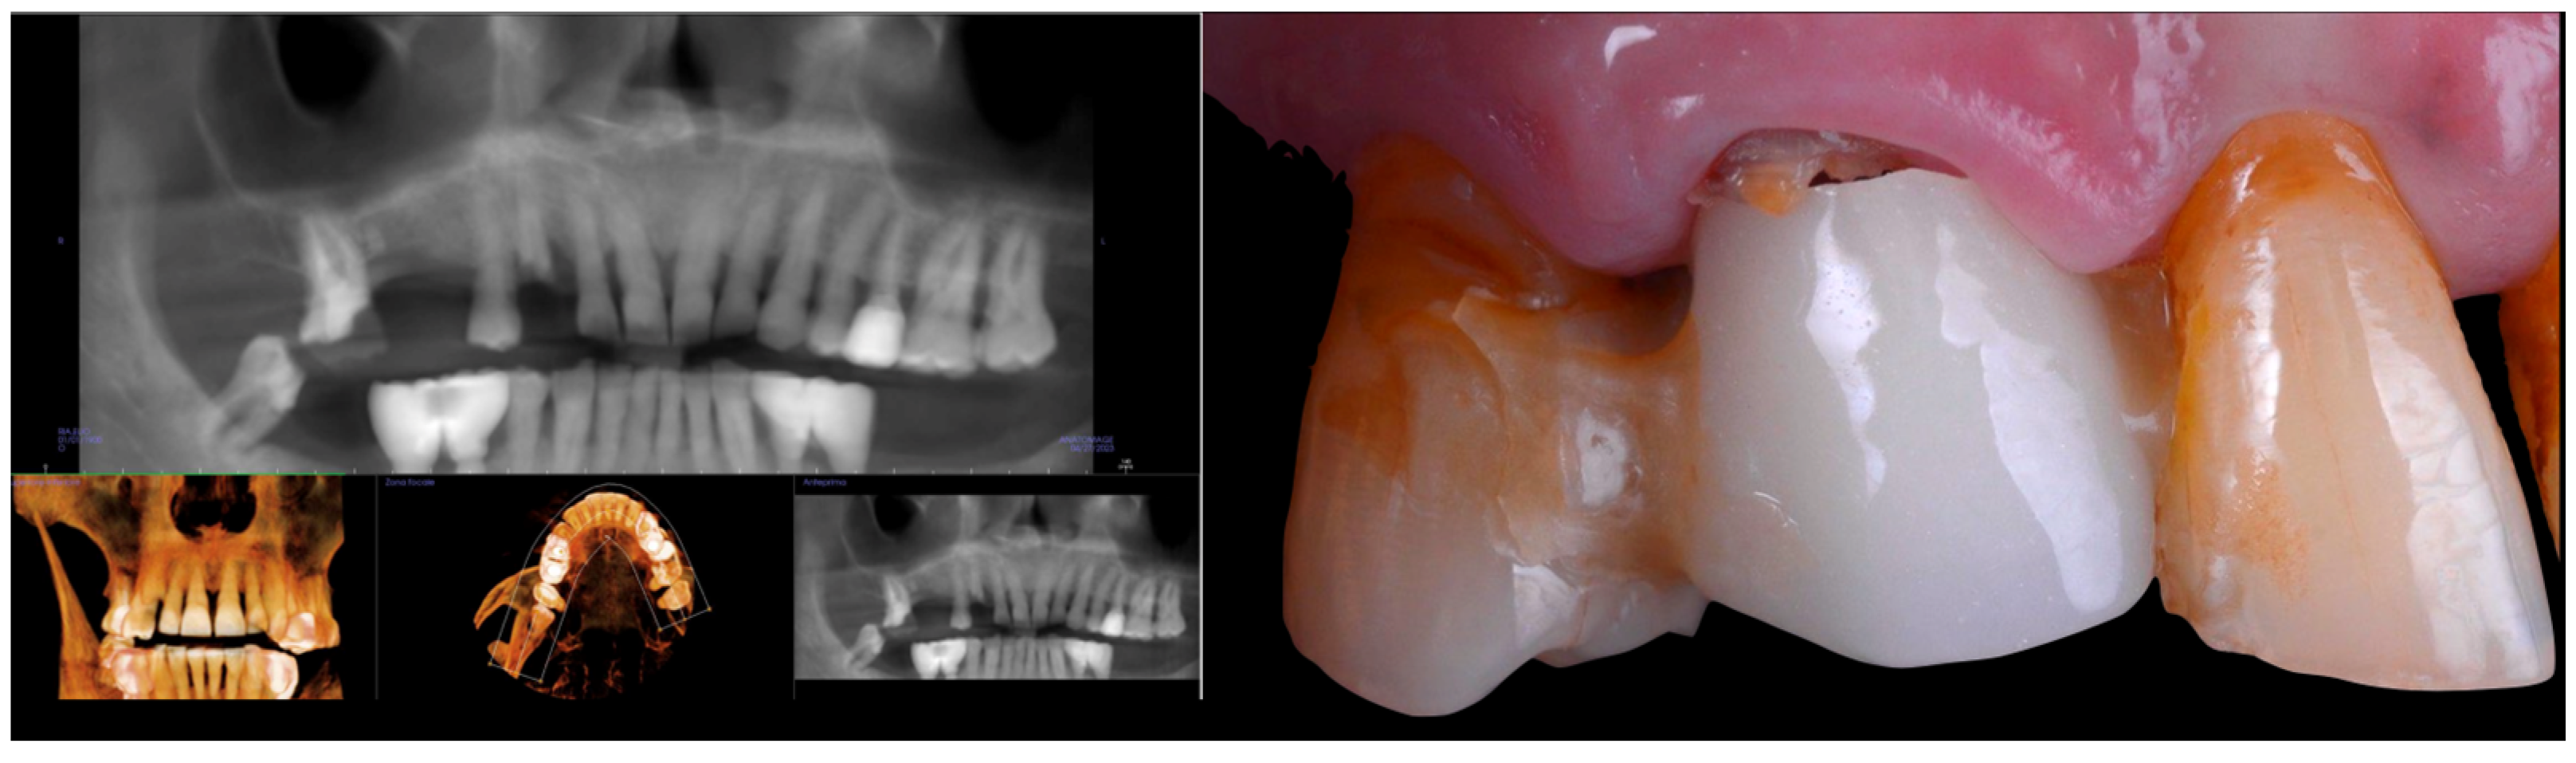

2.1. Case Presentation

2.2. Surgery